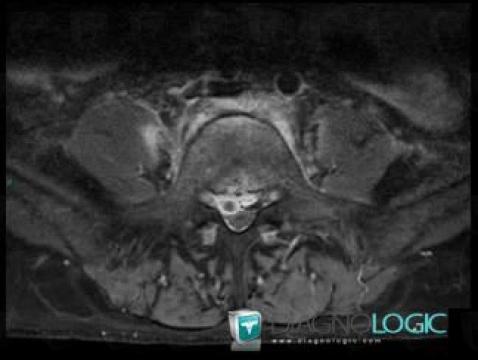

Spondylodiscitis, Spinal canal / Cord, MRI

Here is the specific information in the key image above:

- Diagnosis Spondylodiscitis, Location(s) Spinal canal / Cord, with gamuts Extradural lesion

Abscess, Spinal canal / Cord, MRI

- Diagnosis Abscess, Location(s) Spinal canal / Cord, with gamuts Extradural lesion